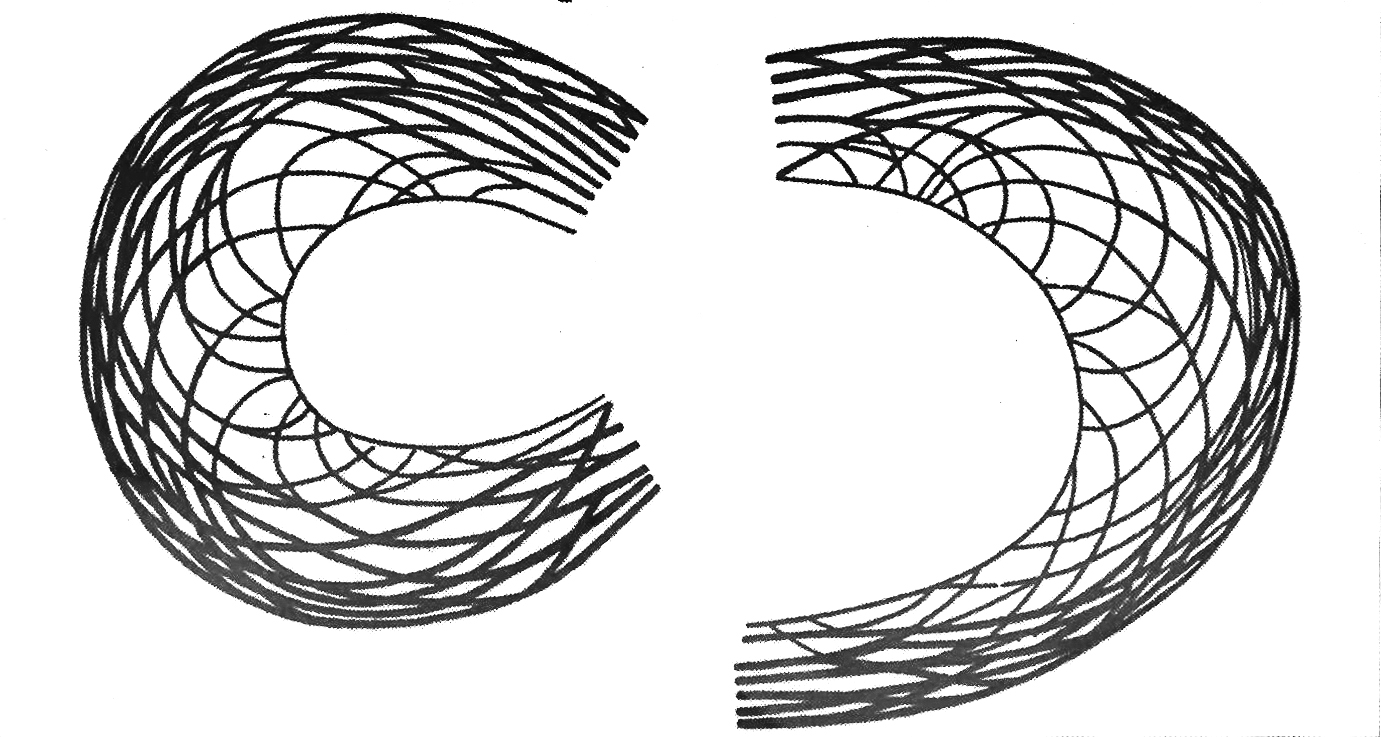

Ο μηνισκικός ιστός είναι μια εξωκυτταρική θεμέλιος ουσία, αποτελούμενη 65-75% από νερό, 20% κολλαγόνο τύπου Ι και 5% άλλες οργανικές ουσίες, όπως πρωτεογλυκάνες, γλυκοπρωτεΐνες και ελαστίνη. Το κολλαγόνο αποτελεί το 75% του αφυδατωμένου μηνίσκου, οι ίνες του οποίου διαπλέκονται κυκλοτερώς, κυρίως στην περιφέρεια και την κάτω επιφάνεια του μηνίσκου, και εγκαρσίως προσδίδοντας αντοχή σε συμπιεστικές και διατμητικές δυνάμεις (εικόνα 2).